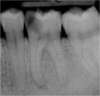

Exemple:

Une volumineuse carie s’est développée sur cette molaire inférieure. L’envahissement bactérien de la pulpe oblige le chirurgien-dentiste à nettoyer et désinfecter entièrement la cavité pulpaire (chambre pulpaire et canaux radiculaire), jusqu’aux extrémités des racines. Cet espace ainsi préparé est ensuite obturé de façon étanche (matériau blanc sur les radiographies).